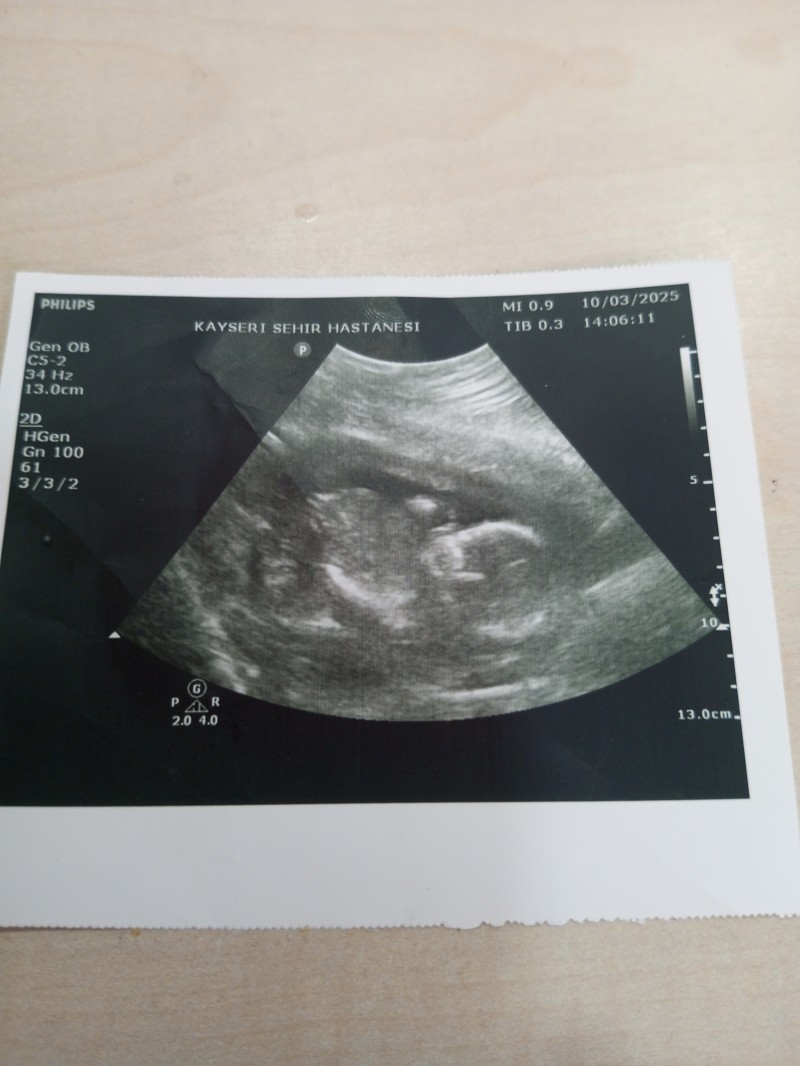

Cinsiyet tahmini yaparmısınız

Resim bu canlar

Maşallah. Kaç haftalık? Kız bence

Ultrasonda 15 flan olması lazjm suab 26 haftalık olduk ama hala cinsiyeti beli değil bacaklari kapalı tahminen kız diyorlar m net bsey yok hala

Fotuya bakar bakmaz içime kız doğdu ondan kız diyorum

Bence kız ama hayırlısı olsun inşallah kardeşim, ilk gebeliğin mi